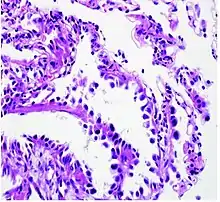

Histopathology

Adenocarcinoma of the lung tends to stain mucin positive as it is derived from the mucus-producing glands of the lungs. Similar to other adenocarcinoma, if this tumor is well differentiated (low grade) it will resemble the normal glandular structure. Poorly differentiated adenocarcinoma will not resemble the normal glands (high grade) and will be detected by seeing that they stain positive for mucin (which the glands produce). Adenocarcinoma can also be distinguished by staining for TTF-1, a cell marker for adenocarcinoma.[29]

As discussed previously, the category of adenocarcinoma includes are range of subtypes, and any one tumor tends to be heterogeneous in composition. Several major subtypes are currently recognized by the World Health Organization (WHO)[1] and the International Association for the Study of Lung Cancer (IASLC) / American Thoracic Society (ATS) / European Respiratory Society (ERS):[30][31][32] lepidic predominant adenocarcinoma, acinar predominant adenocarcinoma, papillary predominant adenocarcinoma, micropapillary predominant adenocarcinoma, solid predominant adenocarcinoma, and solid predominant with mucin production. In as many as 80% of these tumors, components of more than one subtype will be recognized. Surgically resected tumors should be classified by comprehensive histological subtyping, describing patterns of involvement in increments of 5%. The predominant histologic subtype is then used to classify the tumor overall.[2] The predominant subtype is prognostic for survival after complete resection.[33]

To reveal the adenocarcinomatous lineage of the solid variant, demonstration of intracellular mucin production may be performed. Foci of squamous metaplasia and dysplasia may be present in the epithelium proximal to adenocarcinomas, but these are not the precursor lesions for this tumor. Rather, the precursor of peripheral adenocarcinomas has been termed atypical adenomatous hyperplasia (AAH).[10] Microscopically, AAH is a well-demarcated focus of epithelial proliferation, containing cuboidal to low-columnar cells resembling club cells or type II pneumocytes.[10] These demonstrate various degrees of cytologic atypia, including hyperchromasia, pleomorphism, prominent nucleoli.[10] However, the atypia is not to the extent as seen in frank adenocarcinomas.[10] Lesions of AAH are monoclonal, and they share many of the molecular aberrations (like KRAS mutations) that are associated with adenocarcinomas.[10]